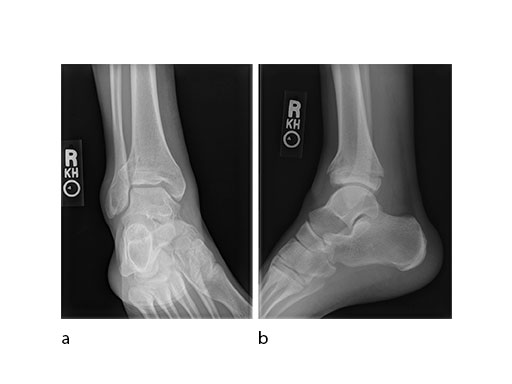

A 17-year-old male patient was involved in a snowboarding accident. This was a closed injury, and he was initially splinted for 10 days. His injury pattern demonstrated anterior articular impaction (Fig 1).